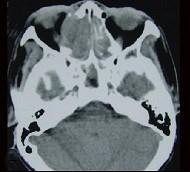

问题 女性,53岁,右侧鼻腔流血近1年,近来头痛,行CT检查如图所示,请选择正确的答案()

选项 A.鼻腔癌 B.鼻腔内息肉 C.副鼻窦炎 D.鼻腔炎性假瘤 E.鼻腔内血管瘤

答案 A